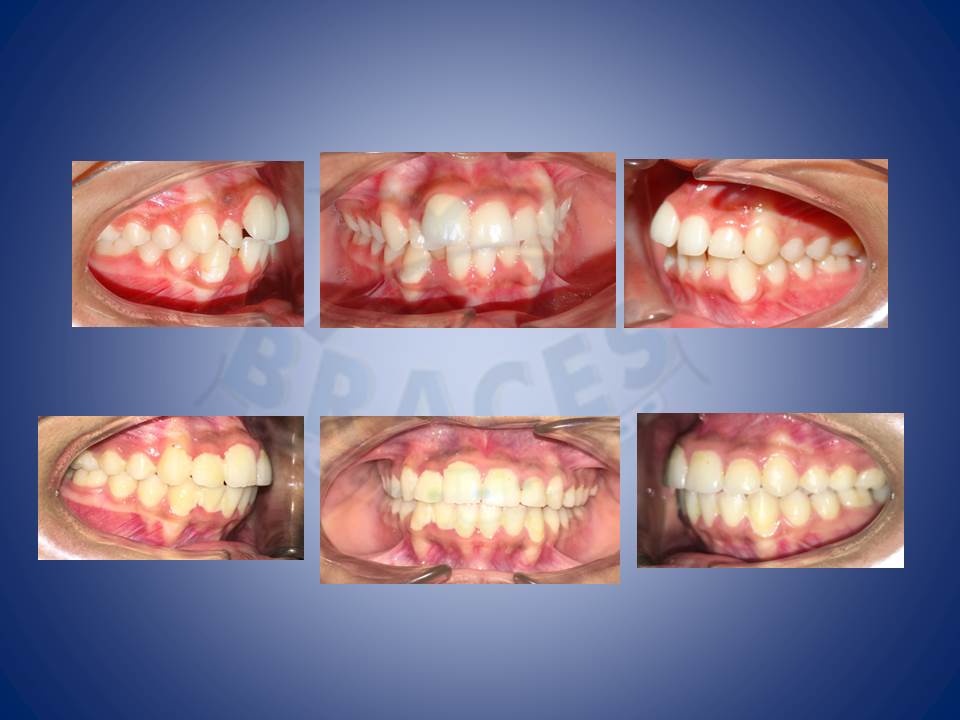

3.Molar distalisation though difficult can be very well done in cases where excessive spaces are required and no extractions can be afforded. Here a palatal Miniscrews was used and distalisation was done with coil springs.

4.Dental spaces are better corrected witht the help of braces in comparison to artificial means like fillings and crowns.

5.Surgical cases wherein the jaw is back or forward can be well camouflaged with the help of mechanics unique to DG BRaces learnt under Dr. Federico Nadela following COTS protocal.